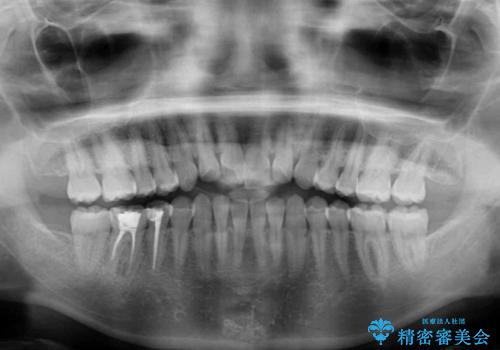

- 上下の前歯の反対咬合を気にして来院された患者様です。

インビザラインを用い、下顎はIPR(歯と歯の間を削る)と歯列全体を後方に移動させ、上顎は前歯を持ち上げることで、反対咬合を改善していくこととしました。